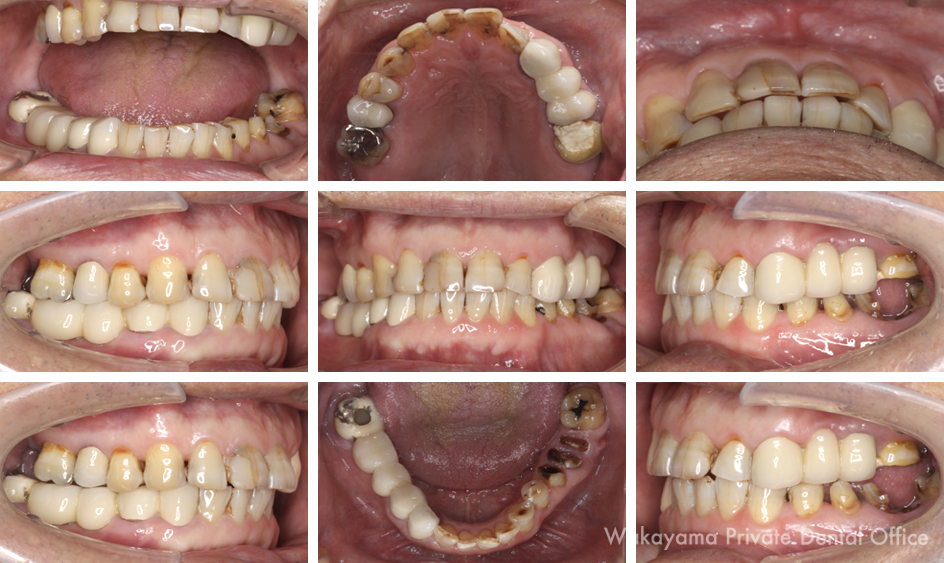

症例⑥ 60代男性 咬合バランスも踏まえたインプラント治療

1) 治療前

昔から歯には自信があったが、年々少しずつ歯が悪くなりもっとしっかりと噛めるようになりたいとのことで来院されました。部分的な治療を続けて来られたので、全体のバランスが崩れてしまっています。

5) 治療前後のお口の中の比較

噛み合わせもバランスも整い、左右対称な被せ物でしっかりと噛める状態になりました。今後、この状態をキープするためにしっかりとメインテナンスを続けていく必要があります。

主訴 年々少しずつ歯が悪くなり、もっとしっかりと噛めるようになりたいです。

治療期間 6ヶ月

治療費 総額420万円(税別)

治療内容 噛み合わせ治療、インプラント治療。残すことが出来る歯はしっかりと処置をした上で保存し、形や硬さなど全体のバランスを整えました。見た目だけではなく、食事もしっかり楽しむことができる機能美を得ることが出来ました。